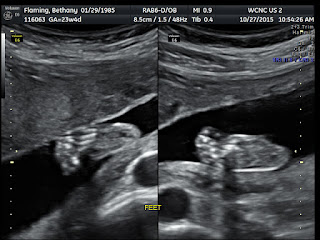

Baby Anatomy Scan

Today we went in for Baby Flaming's anatomy scan. They checked out and measured in detail every organ and body part including the baby's heart, brain, kidneys, bowels, facial features, hand, feet, arms and legs. Baby Flaming is perfectly healthy and growing right on track. Thank you Lord for answered prayers!!

The Big Reveal............ It's a GIRL!!!

| Her sweet little face- Todd says she has my lips |

Todd and I are so excited and blessed to welcome this little bundle of sweet joy into our lives.